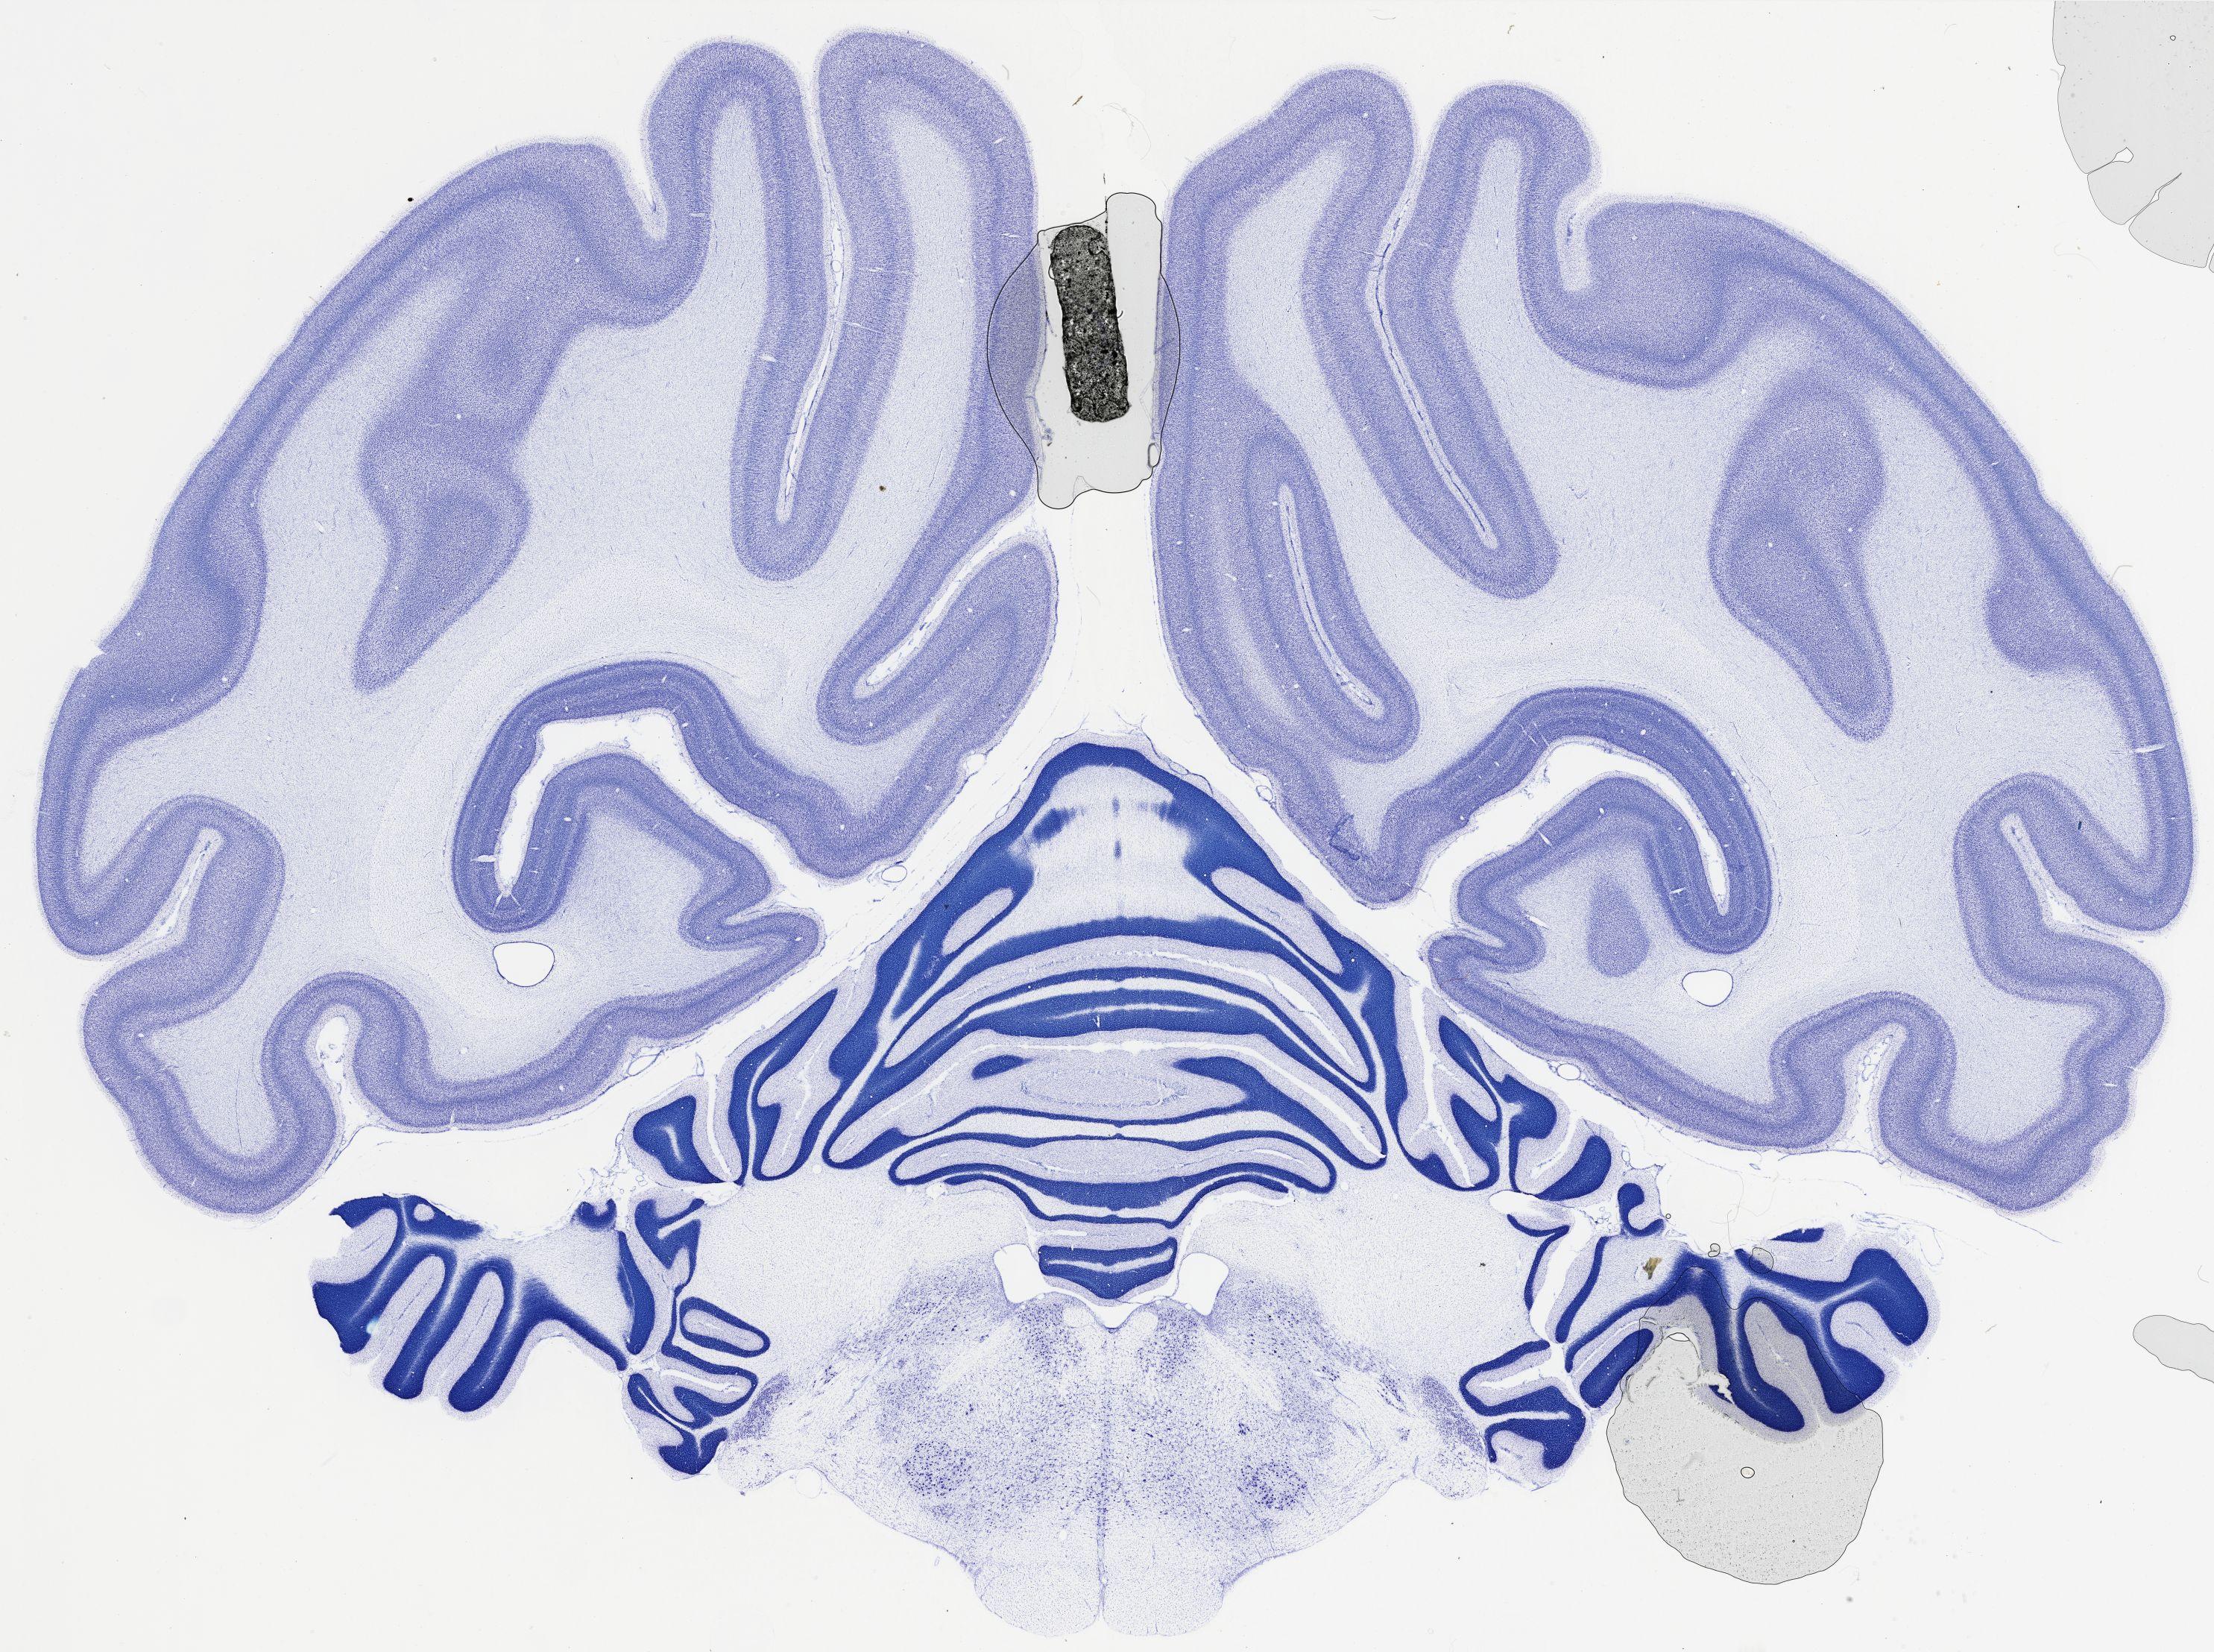

Datasets -> Chlorocebus Aethiops -> Nissl, coronal, histo, Whole-Brain, adult

[ Metadata ]   ·   Source: NeuroScience Associates

thumbnail

521